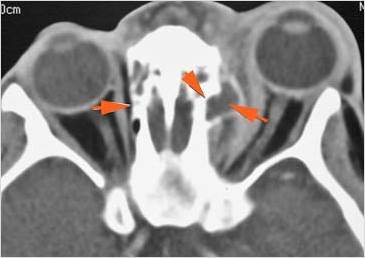

Orbits

There is a subperiosteal abscess or edema along the medial wall, roof or floor of the orbit. [Yes/No]

The extraocular muscles are swollen or otherwise abnormal. [Yes/No]

The orbital apex and the superior and inferior orbital fissures are infiltrated. [Yes/No]

The superior and/or inferior ophthalmic veins are dilated or thrombosed. [Yes/No]